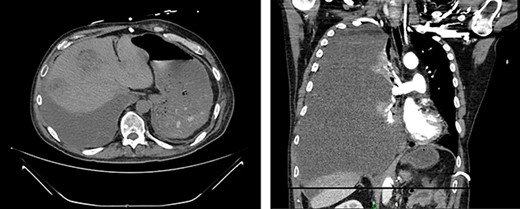

Left renal mass measuring 11 × 9 × 7cm in transverse (left) and coronal (right) planes.

A 52-year-old, previously healthy, Caucasian male presented to the emergency department (ED) with chief complaints of gross hematuria, abdominal pain, vomiting, diarrhea and left flank pain for 3 days. He had neither family history of cancer nor history of exposure to ionizing radiation, arsenic, thorium dioxide or vinyl chloride. He reported exposure to chemical tankers 10 years prior and had recent occupational exposure to paint-thinning agents. Urinalysis on admission showed large blood with later cytology significant for atypical epithelioid cells concerning for neoplasm of the kidney or bladder. Subsequent contrast-enhancedcomputed tomography (CT) of the abdomen revealed an 11-cm left renal mass, 2-cm para-aortic lymphadenopathy and possible invasion of the tail of the pancreas (Fig. 1). He was then referred to urology for evaluation and to discuss treatment options.